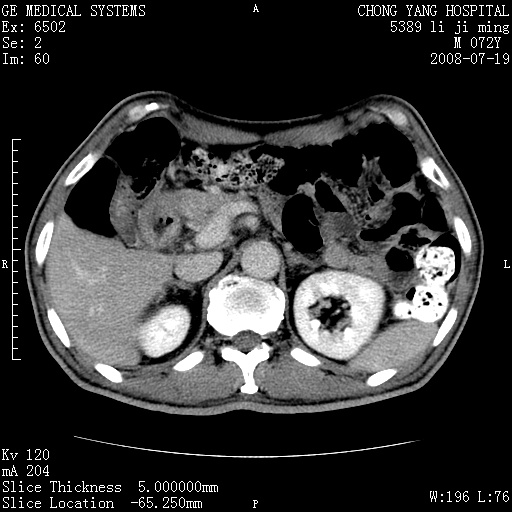

以下是引用zjzjr在2008-7-19 20:57:00的发言:[br]胰头增大,边缘模糊,周围可见渗出影,右侧肾前筋膜增厚.支持胰腺炎.

以下是引用yangyudong333在2008-7-20 6:56:00的发言:[br]胰腺增大尤以胰头明显,边缘模糊,周围可见渗出影,右侧肾前筋膜增厚,肠管於涨.支持胰腺炎

以下是引用不学无术在2008-7-19 23:15:00的发言:[br]胰腺增大尤以胰头明显,边缘模糊,周围可见渗出影,右侧肾前筋膜增厚,肠管於涨.支持胰腺炎